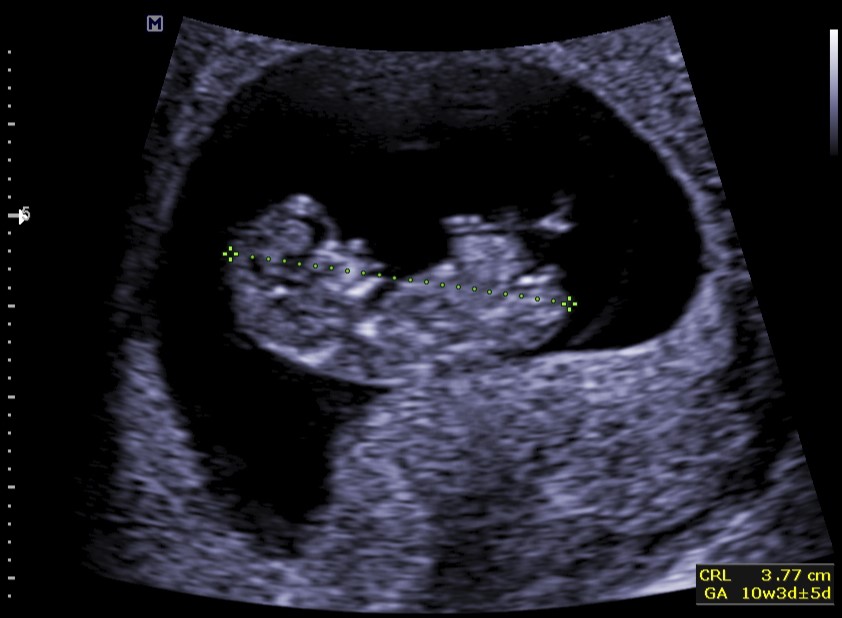

Termijnecho

De termijnecho is bedoeld om de exacte zwangerschapsduur en dus de uitgerekende datum te bepalen. Bij voorkeur wordt deze echo rond 11 weken zwangerschap gemaakt. Aan de hand van de grootte van de foetus kan de zwangerschapsduur vrij nauwkeurig worden berekend.

Daarnaast kijken we naar de aanwezigheid van hartactie, of de zwangerschap zich in de baarmoeder bevindt en of er sprake is van een- of meerlingzwangerschap.

De termijnecho wordt in principe via de buikwand gemaakt. Hiervoor is het handig dat je een gevulde blaas hebt. Een gevulde blaas zorgt ervoor dat de baarmoeder iets omhoog wordt geduwd waardoor deze via de buik duidelijker te zien is. Mocht het beeld toch niet optimaal zijn, dan kan het voorkomen dat we de echo vaginaal willen maken. Door een inwendige echo kunnen we dichter bij de baarmoeder komen waardoor het beeld vaak duidelijker wordt.